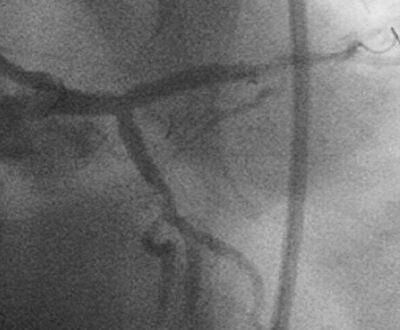

高度石灰化#1~#2と同#6/#9に対するRotablator依頼で他院から紹介され、PCIを

施行した86歳の男性です。3日前にRCAへRota-SESして、今回#6/#9へのPCIでした。

Baselineが『ChoicePT2BsLn』の3枚です。

7F lTFA(Arrow金属シース55cm)で7F Mach1 CLS4.0を使用、#9→#6の順に1.5mm burr

でRotablatorを行ない、2.0mmへサイズアップしました。2.5mmバルーンで#9→#6と拡

張し、#6に3.5mm×23mmのCypherを留置しました。3.5mmバルーンで#6を高圧(最

大22ATM)後拡張し、#9の2.5mmバルーンとともにSimultaneous kissing inflationを

施行、#6、#9ともに良好な開大を得ました。

しかし、KBT直前の像(『ChoicePT2.GW.Prolapse』)では屈曲していただけの#9に挿

入したChoice PT2 LSが、KBT時像からは屈曲とともに先端1cm程度が断裂し

(『ChoicePT2.GW.Fracture』)、#9の末梢枝に遺残してしまいました

(『ChoicePT2.Fnl』2枚)。幸い虚血所見がまったくありませんでしたので手技は終

了とし、術後のCK逸脱もなし、翌日お元気に退院されました。